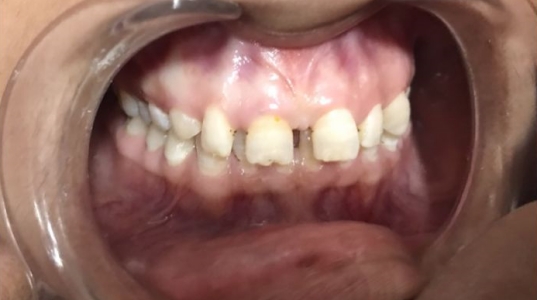

At Pranjal Dental Clinic, we offer a wide range of advanced dental treatments in Greater Noida to ensure complete oral health and beautiful smiles. Our services include root canal treatment, dental implants, smile designing, teeth whitening, cosmetic dentistry, tooth extraction, and painless dental care. With modern technology and expert care by Dr. Pranjal Sirohi, we provide safe, effective, and comfortable dental solutions for patients of all ages.